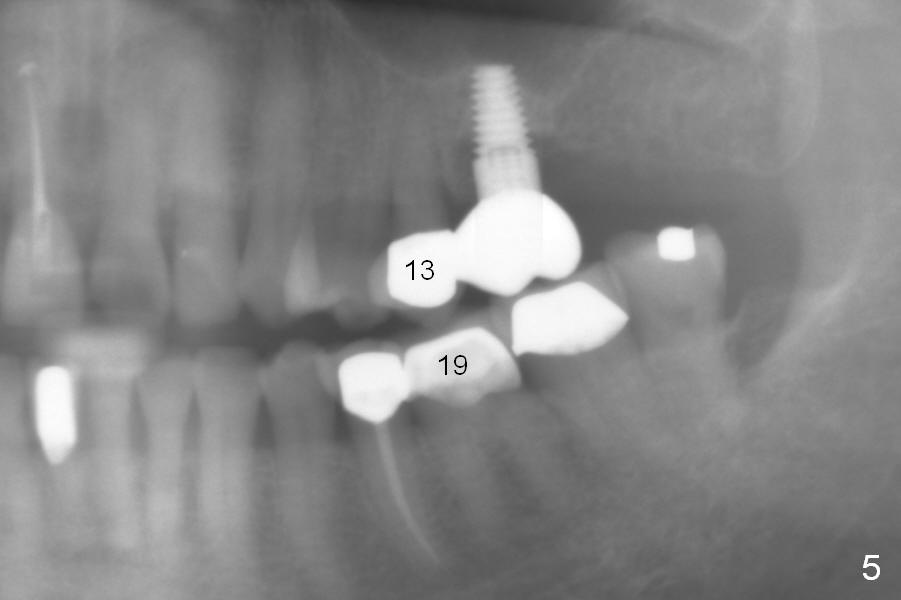

A 73-year-old woman is a possible bruxer with partial edentulism; the tooth #13 had increased periodontal ligament (pdl) space 4 years ago (Fig.1 *).  A 5x14 mm tissue-level implant is placed at the site of #14 (Fig.2).  The implant appears to be osteointegrated in 6 months (Fig.3).  There is crestal bone loss 8 months post cementation (Fig.4 *).  The persistent increased pdl at #13 is most likely associated with occlusal tramua from the tooth #19 (Fig.5 (13 months post cementation of #14)).  Three years post #14 cementation, the tooth #13 has mobililty II (Fig.6); bone density increases around the apical half of the implant (arrowheads).  Normally bone density is the highest coronally where functionality dictates.  This indicates the bone loss is getting worse at #14 as well.